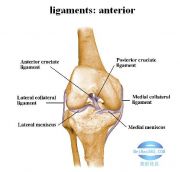

| 2021年7月26日 (一) 20:03 | 膝关节韧带前面观.jpg (文件) |  |

33 KB | Uploaded with SimpleBatchUpload | 3 |